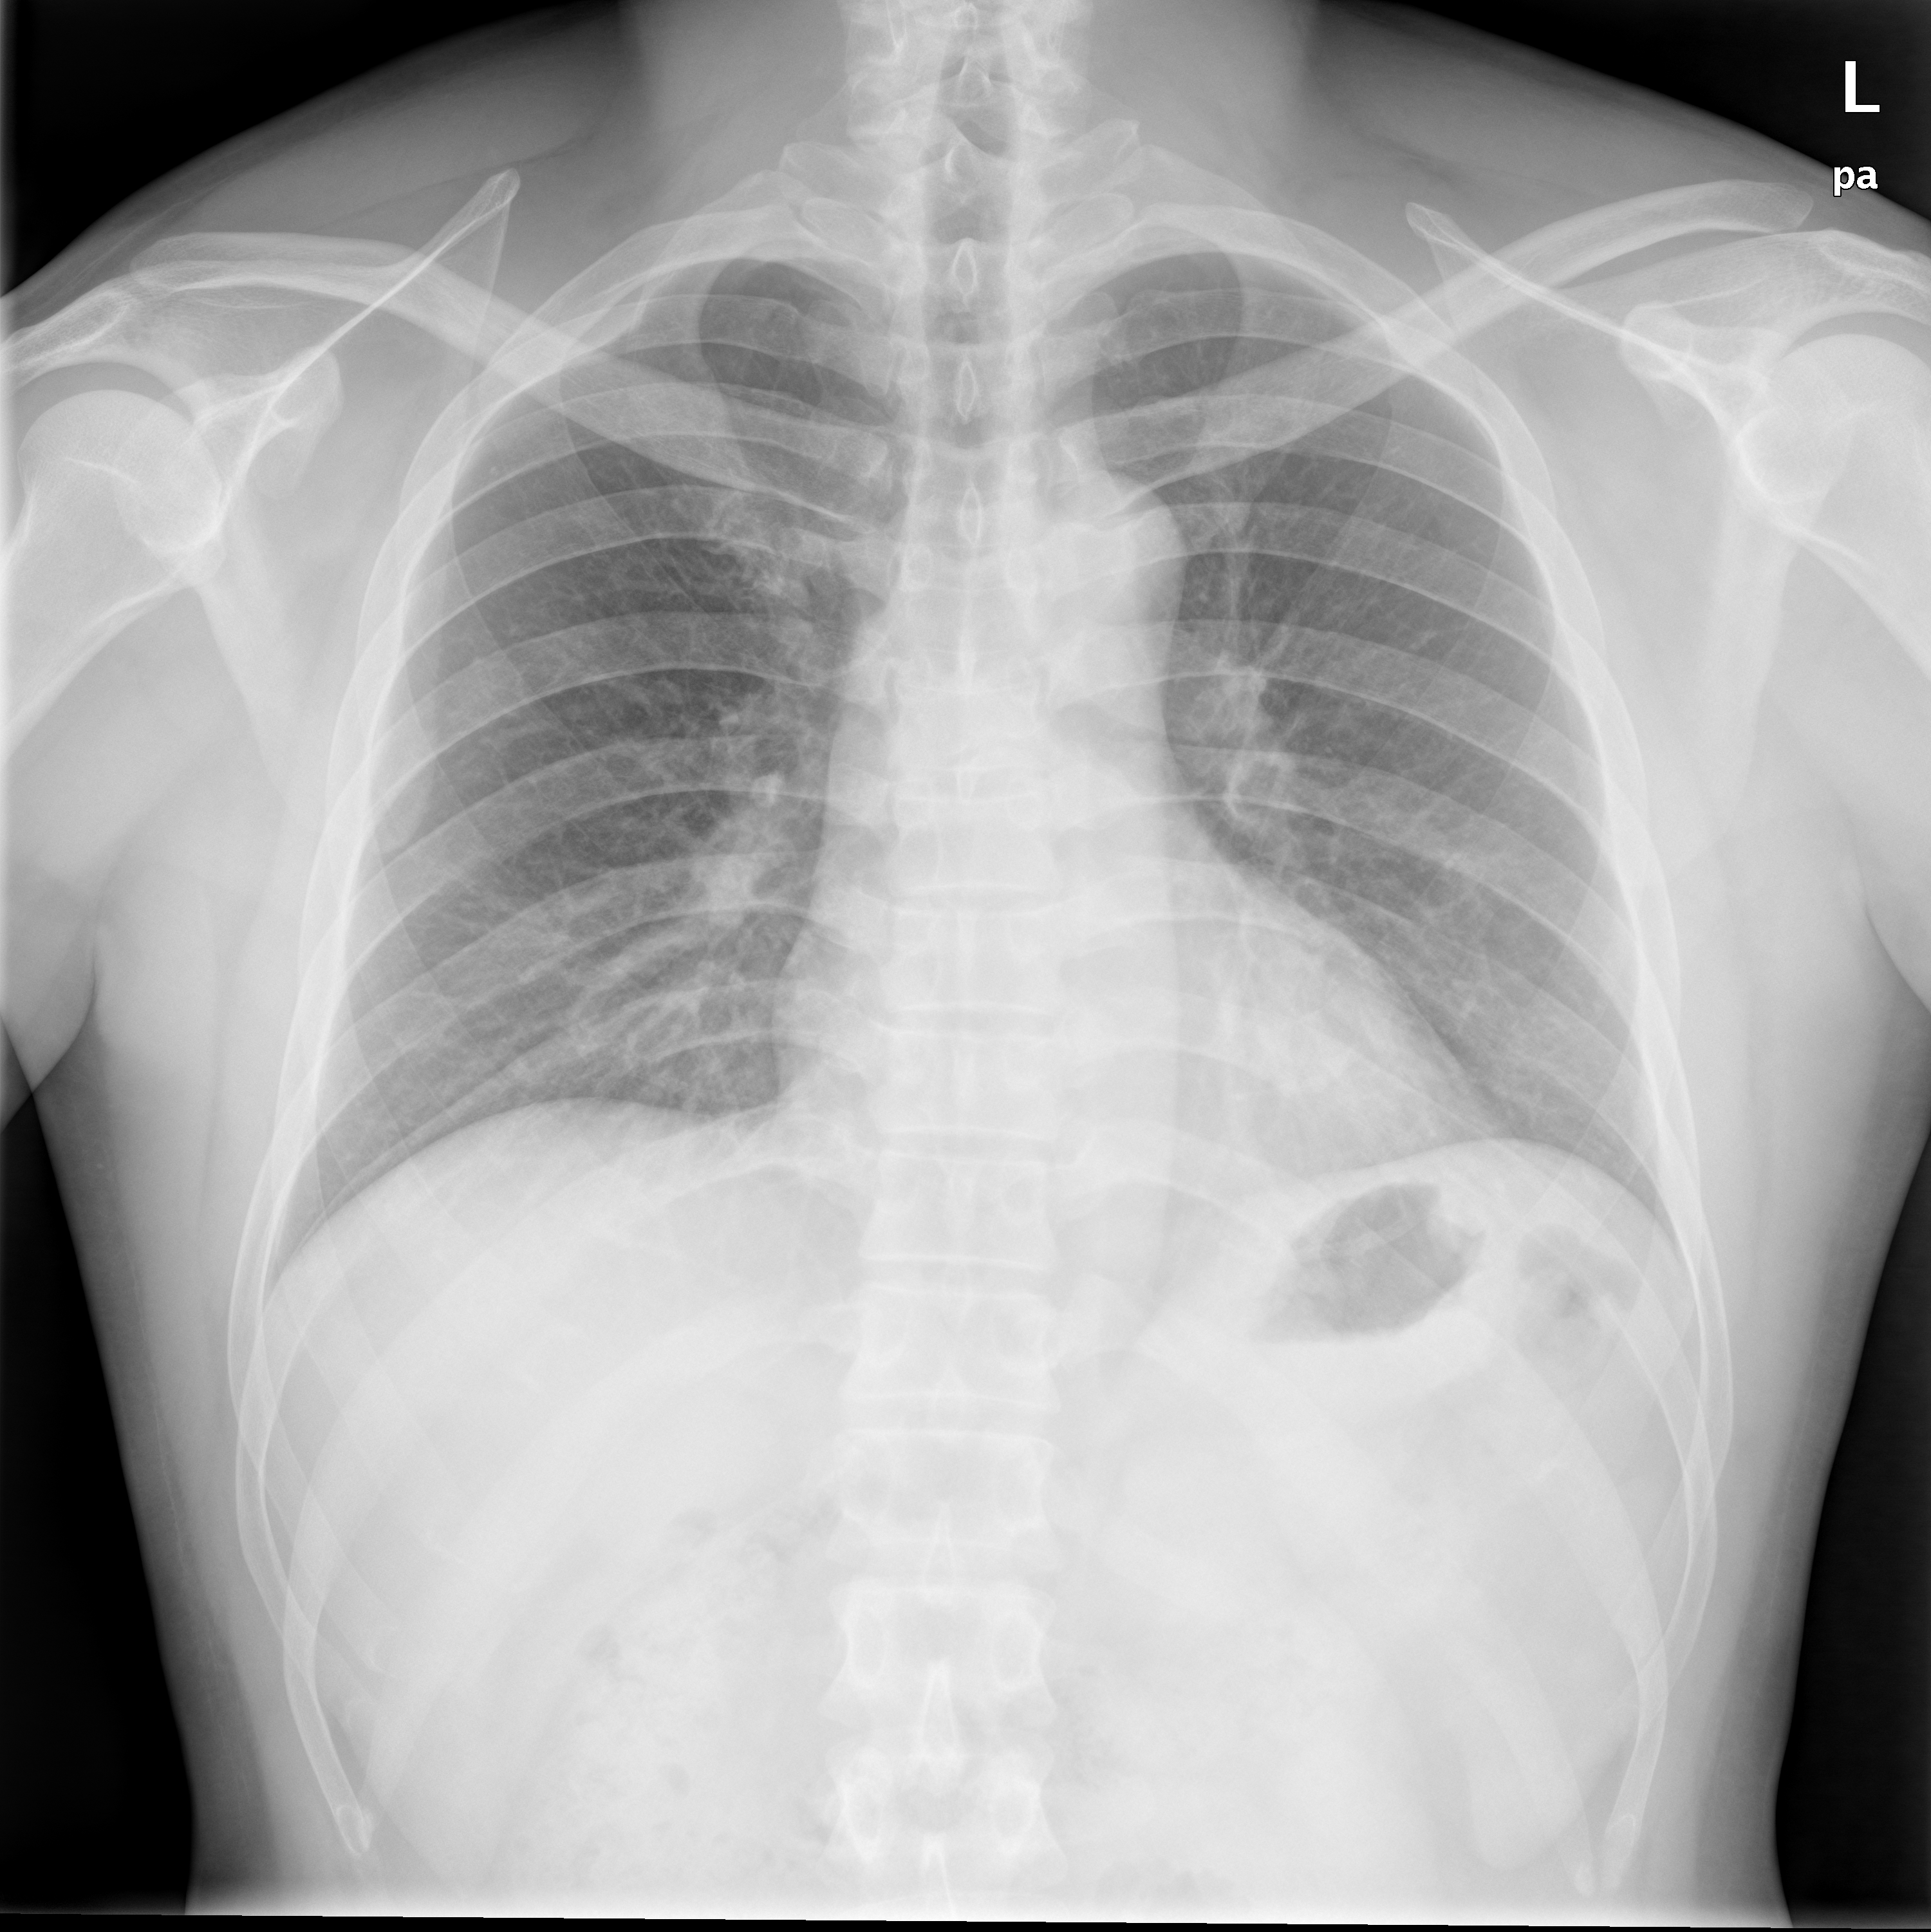

Practice Tuberculosis (TB) Diagnosis

CHNCXR_0216_0.png

0 - Normal